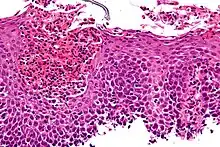

Microscopic Slide of Eosinophilic Esophagitis

Eosinophilic esophagitis

Eosinophilic esophagitis is caused by a high concentration of eosinophils in the esophagus. The presence of eosinophils in the esophagus may be due to an allergen and is often correlated with GERD. The direction of cause and effect between inflammation and acid reflux is poorly established, with recent studies (in 2016) hinting that reflux does not cause inflammation.[6] This esophagitis can be triggered by allergies to food or to inhaled allergens. This type is still poorly understood.